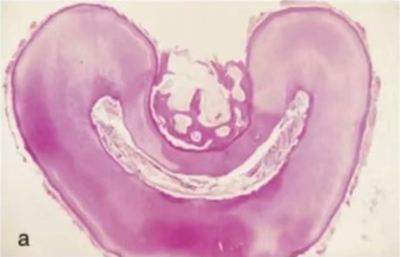

在一項(xiàng)包含了 149例下頜第二磨牙的研究中,Manning 發(fā)現(xiàn) 76%的下頜第二磨牙為雙根,22%為單根,2%為三根。在另一項(xiàng) Vertucci 報(bào)道的包含了 100 例下頜第二磨牙的研究中,近中根中,單根管為 27%,雙根管融合為單根管為 38%,兩個(gè)獨(dú)立的根管為 35%。遠(yuǎn)中根中,Vertucci發(fā)現(xiàn) 92%為單根管,兩根管融合為單根管為 3%,兩個(gè)獨(dú)立的根管為 5%)。Beatty 和 Krell 報(bào)道了一例下頜第二磨牙遠(yuǎn)中根三根管的病例。下頜第二磨牙單根與雙根的根管結(jié)構(gòu)可能相同,或也都可能為 C 型根管系統(tǒng),其以獨(dú)立的根管間存在弧形或網(wǎng)狀峽區(qū)為特征。C 型牙根和根管系統(tǒng)的形成可能與牙根頰側(cè)或舌側(cè)表面的 Hertwig 上皮根未融合或不完全融合相關(guān)。白種人中 C 型根管的發(fā)生率在2.7%~7.6%;

但是,在其他的種族中,C 型根管的發(fā)生率可能會(huì)明顯的升高,如在中國(guó)人中,發(fā)生率可能高至 31.5%。C 型根管也可能存在多種變異形態(tài)。Fan 等人,使用顯微 CT 檢查了 58 例下頜第二磨牙的 C 型根管結(jié)構(gòu),掃描范圍從髓室至根尖,間隔0.5mm。

根據(jù)不同層面根管截面的形狀,C 型根管被分為如下 5 類:

C1:根管橫截面形態(tài)為連續(xù)不間斷的 C 型;

C2:C 型根管輪廓中斷呈分號(hào)狀;

C3:根管數(shù)目為 2 或 3 個(gè),其中存在峽部連接;

C4:根管截面為圓形或橢圓形;

C5:截面未觀察到管腔形態(tài)。

大部分 C 型根管系統(tǒng)在根管口處為連續(xù)的 C 型結(jié)構(gòu);但是,沿著牙齒牙根方向,橫截面形狀可能是 C1,C2 或 C3 的任一種。C4 和 C5 幾乎只能在根尖附近的橫截面見到(圖 15a-c)。C 型根管的下頜磨牙在清理、預(yù)備成型及充填方面都存在挑戰(zhàn),特別是,當(dāng)髓室底發(fā)現(xiàn)C 型根管口時(shí),不能確定根管在到達(dá)牙根根尖 1/3 時(shí)是否是連續(xù)的。在定位 C 型根管系統(tǒng)主根管分叉為兩根管或三根管的部位及識(shí)別根管間的峽部時(shí),手術(shù)顯微鏡是很有幫助的(圖16a-b)。C 型根管沖洗時(shí)應(yīng)盡量使用超聲銼活化沖洗液。